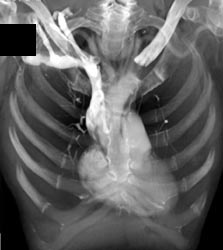

Osteiod Osteoma With Prior Failed Biopsy